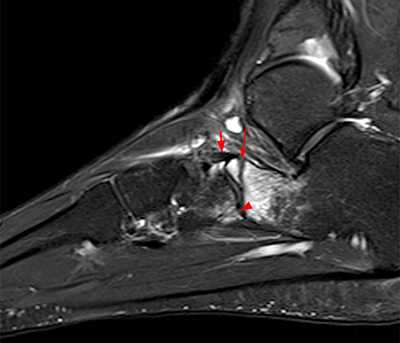

Рентгенологическое исследование

Для диагностики повреждения сустава Шопара делают рентген, КТ и МРТ. На передне-задней рентгенограмме определяют величину пяточно-кубовидного угла. Проводят одну касательную к наружному краю кубовидной кости и вторую касательную к наружному краю пяточной кости. В норме угол между касательными колеблется в пределах от 0 до 5°. Увеличение угла свидетельствует о нарушении стабильности пяточно-кубовидного сочленения. КТ во фронтальной и сагиттальной плоскостях позволяет выявить дефект суставных фасеток, смещение костей при вывихе и фрагментацию костей при переломе. КТ, по сравнению с рентгенографией, является более информативным методом диагностики. МРТ позволяет выявить дефекты отдельных связок.

Рис. 8. Переломо-вывих в суставе Шопара

Рис. 9. Переломо-вывих в суставе Шопара